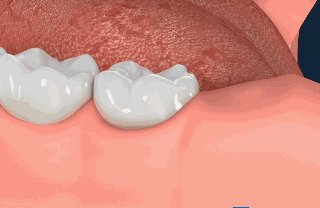

拔牙后的"血窟窿"一词其实是形象化了,听着吓人,在医学上成为牙床,它是可以愈合的,只是需要时间。愈合的过程也是牙齿组织再生的过程。

拔牙后的15分钟:血液凝块凝结

医生在拔除牙齿之后的15分钟,牙齿创口中血液会迅速聚集在伤口处凝结成血块就像平时我们身体其他地方磕碰流血的道理一样,血块凝结覆盖牙槽窝只是发自人体本能保护伤口形成保护膜,预防细菌侵袭感染。而为了促进凝血块的形成,这时,医生一般会让患者咬着棉花球30至40分钟。

24小时后:组织纤维"驻扎"血凝块

当血凝块产生之后,组织纤维开始慢慢"驻扎"进血凝块之中形成血凝块有机化,这是为了更好的保护牙齿预防细菌感染,在24小时之内不可以漱口、吸烟、喝酒。此时牙槽内部依然处于脆弱的阶段,稍加不注意,就会使血凝块脱落,引发牙槽二次出血的状况。

3天至5天后:上皮组织逐渐覆盖牙窝

血凝块有机化后,经过时间的推移,会逐渐转化为肉芽组织,同时牙龈上皮也开始由周围像血凝块表面生长,逐渐覆盖整个创伤表面,这个过程大概需要7天左右,但要全部长好,正常情况下需要一个月。

7天之后骨组织开始重生

拔牙后的每一天创口都在变化,而在第7天后,牙槽窝的新骨逐渐形成,然而新骨从重建到完成则需要3个月至6个月形成。这时的伤口基本愈合。